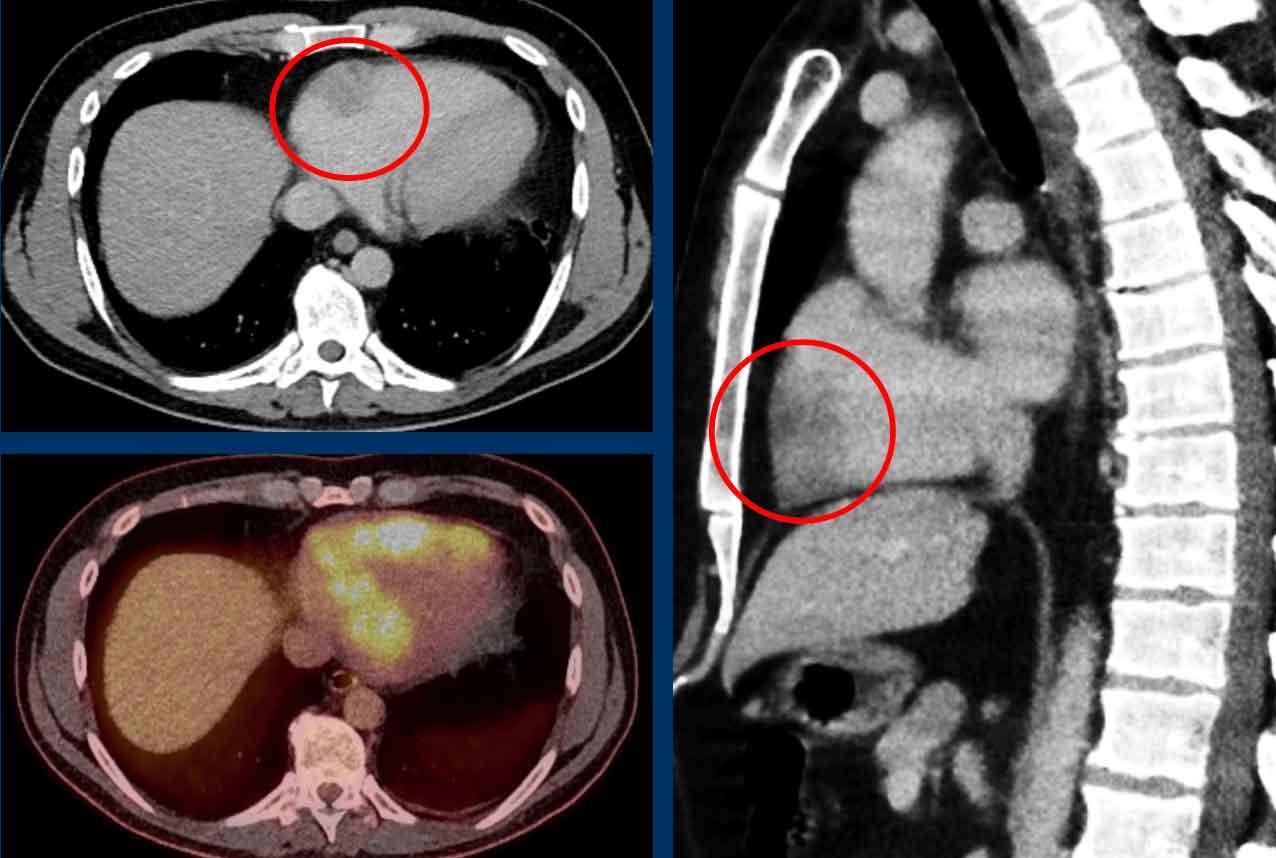

Hình ảnh

Khiếm khuyết tưới máu trong vùng tưới máu của LAD ở bệnh nhân chấn thương 45 tuổi, nhập viện sau khi ngã cầu thang trong lúc khuân vác nặng.

Cài đặt cửa sổ sắc nét hơn giúp đánh giá sự khác biệt tỷ trọng cơ tim.